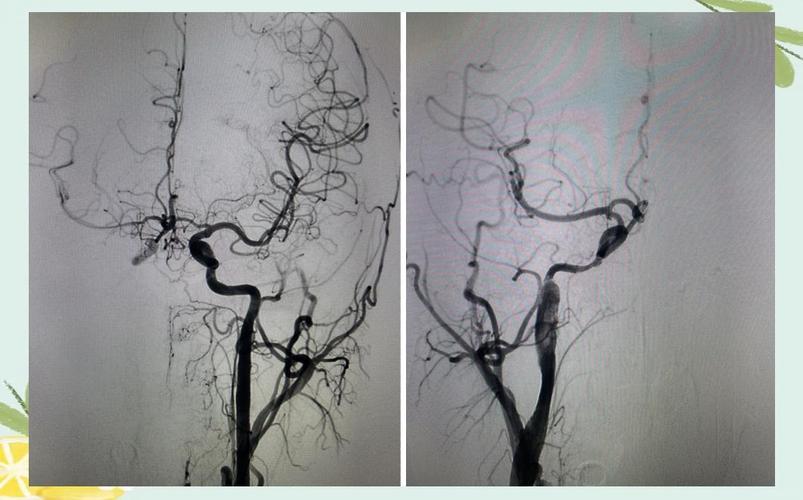

- 技术顶尖:能够独立开展目前国际上最先进的急性缺血性脑卒中血管内治疗技术,如 机械取栓(Thrombectomy),这对于大血管闭塞的脑梗患者来说是决定预后的关键。